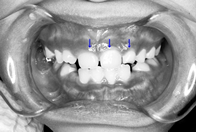

上顎左側の2番目の永久歯(側切歯)が反対咬合です。まだ乳歯も多く残る歯並びですが、全体に凸凹が認められます。

前歯部分の凸凹は上下とも重度であった。乳歯の虫歯も多く、歯磨き練習も重要でした。